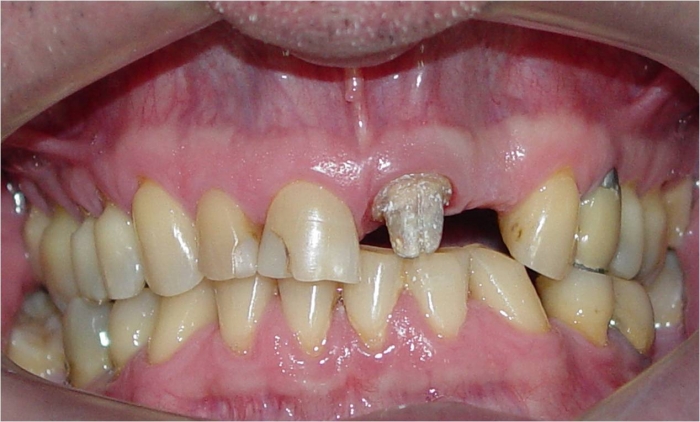

Imagens iniciais, mostrando ausência do elemento 22

Imagem inicial